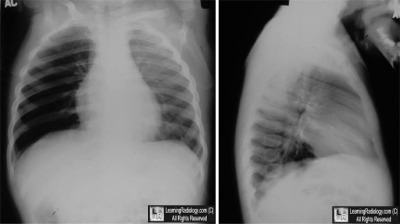

- 16 month-old with wheezing

Frontal and Lateral Chest Radiograph

- Double aortic arch

- Asthma

- Aspirated foreign body

- Croup

- Left pleural effusion

3. Aspirated foreign body